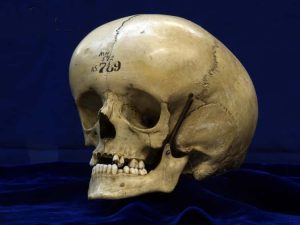

Hydrocefalus je stav, kedy sa vo vašej lebke hromadí voda

Hydrocefalus môže vzniknúť ako dôsledok genetickej poruchy ale aj rôznych iných komplikácií počas tehotenstva. Už podľa názvu si vieme odvodiť, že ide o nadmerné nahromadenie cerebrospinálnej tekutiny v mozgu, čo je problém vzhľadom na zvyšujúci sa tlak vo vnútri lebky.

Lebky dojčiat sa čiastočne dokážu prispôsobiť, nakoľko švy na lebke nie sú ešte do určitého obdobia po pôrode celkom zrastené a osifikované. Väčší problém je u dospelých jedincov, kde je zvyšujúci sa vnútrolebečný tlak sprevádzaný intenzívnymi bolesťami hlavy, stratou zmyslov a dokonca i zmenami osobnosti. Liečba však existuje, no pozor – v prípade jej zanedbania človeku hrozí smrť.